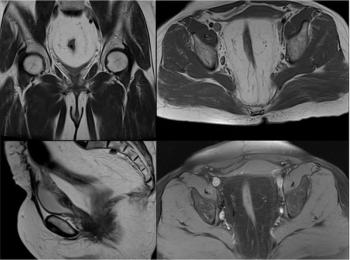

45-year-old woman with nonspecific pelvic pain and fullness, after MRI underwent cystoscopy and biopsy which revealed proliferative cystitis.